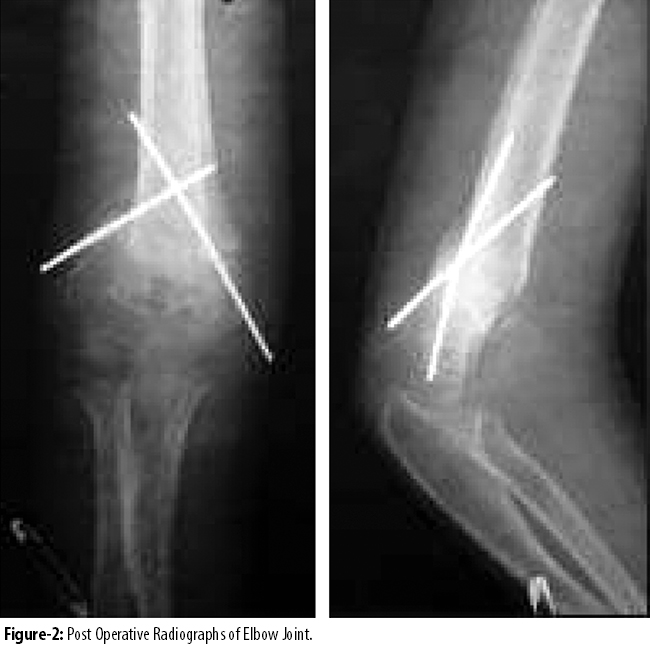

All the operations were carried out with the patients in supine position and the affected arm on a hand table. Pneumatic tourniquet was used. After anaesthetizing, draping of upper limb was done. With anterolateral approach, the supracondylar region of humerus was exposed. The focal dome osteotomy was marked and predrilled. It was completed in the reverse direction by using small osteotome at CORA at supracondylar region of the humerus by applying the principles of deformity correction described by Paley.11 The deformity was corrected and osteotomy was fixed with two cross k-wires. It was protected with above elbow back slab.

Stitches were removed at 2 weeks. Wires and plaster slab were removed at 4 weeks after the surgery and rehabilitation was started. Final assessment of carrying angle (13°-18°) and HUA (15°-20°) and MDA (87°-93°) were done at 8 weeks. The functional and radiological outcome was considered good if the angles were within normal range and poor if the correction was not achieved.